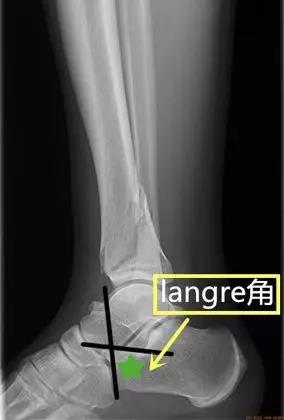

- langre角:在踝关节侧位片或者跟骨侧位片沿跟骨后、中距关节面作一连线,并作跟骨与跟骰关节面连线,此两线相交所形成的角。

- 正常值:约为90°。

- 临床意义:异常提示跟骨骨折。